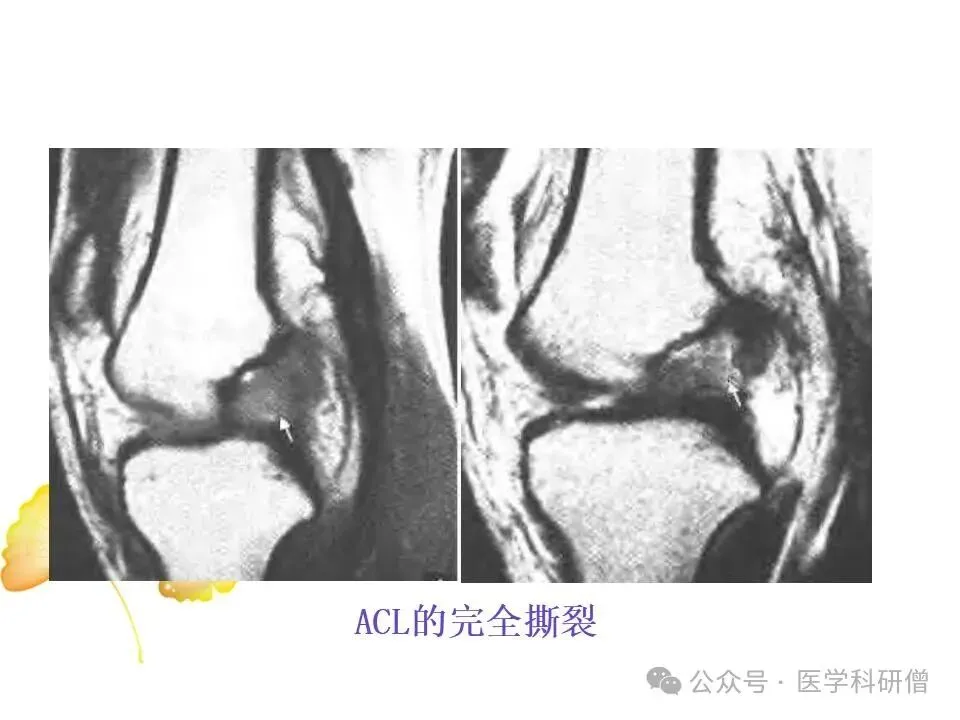

• 前交叉韧带(ACL):位于膝关节内部,负责防止胫骨向前滑动以及控制膝关节的旋转运动。

当膝关节遭受剧烈撞击或扭伤时,上述韧带可能发生拉伤、部分撕裂或完全撕裂,其中ACL损伤最为常见。韧带损伤会导致膝关节稳定性降低,影响日常活动和运动表现。